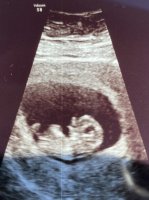

Det var bare 5 dager forskjell så de valgte å ikke endre den. Men fikk ikke samme nei. Hadde det vært stort sprik hadde de sikkert vurdert det da. Men jeg fikk faktisk fastsatt termin på TUL.

Det samme skjedde nylig med min søster. De går ut fra termin som ble satt rundt uke 12 selv om den rundt uke 18 viste noen dager kortere.

Oi, så spesielt! Har eg aldri hørt om faktisk. Og eg syns faktisk det er litt rart, då eg har hørt om kjempe mange som er heilt sikre på unnfangelsesdato, så får dei heilt rare tall på TUL, og så på OUL stemmer det med unnfangelsesdato igjen. 5 dager er jo stor forskjell når det kommer til overtid, og Haukeland av alle burde lært då dei har høgast overtidsdød (eller lika høgt som eit anna) av alle sjukehus i landet då dei lar kvinner gå for langt over termin. Vanskelig balanse de derren ❤

Omtrent på oul termin.

Herlig å bli satt frem to dager også!